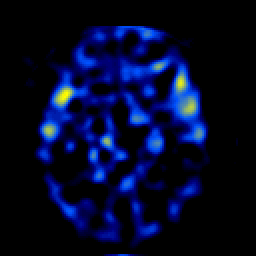

SPECT TL Study #4 -- Slice #25

[Home][Help][Clinical][Tour 1][Tour 2][Tour 3] Slice 25